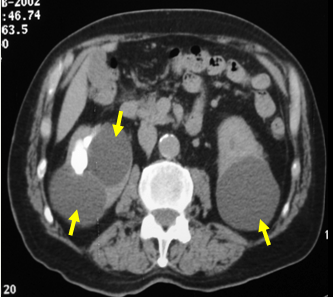

Kidney Cyst On Ct

Possible causes, signs and symptoms, standard treatment options and means of care and support. It is possible to have one or more cysts in one or both kidneys. The kidneys are a powerful filtration system that produce urine. Ct enterography is an imaging test that uses ct imagery and a contrast material to view the small intestine. Kidney cysts are a common but mild problem. The exact cause of simple kidney cysts is not known but they tend to be more common. In this article, learn how prevalent kidney cysts. They filter waste from the blood. Learn more from webmd about simple kidney cysts, including symptoms and treatments. Kidney cysts — round pouches of fluid on or in the kidneys — are sometimes discovered during routine imaging exams. The procedure allows your healthcare provider to determine what is causing your condition. This material must not be used for commercial purposes, or in any hospital or medical facility. Here's an overview of what kidney cysts are.